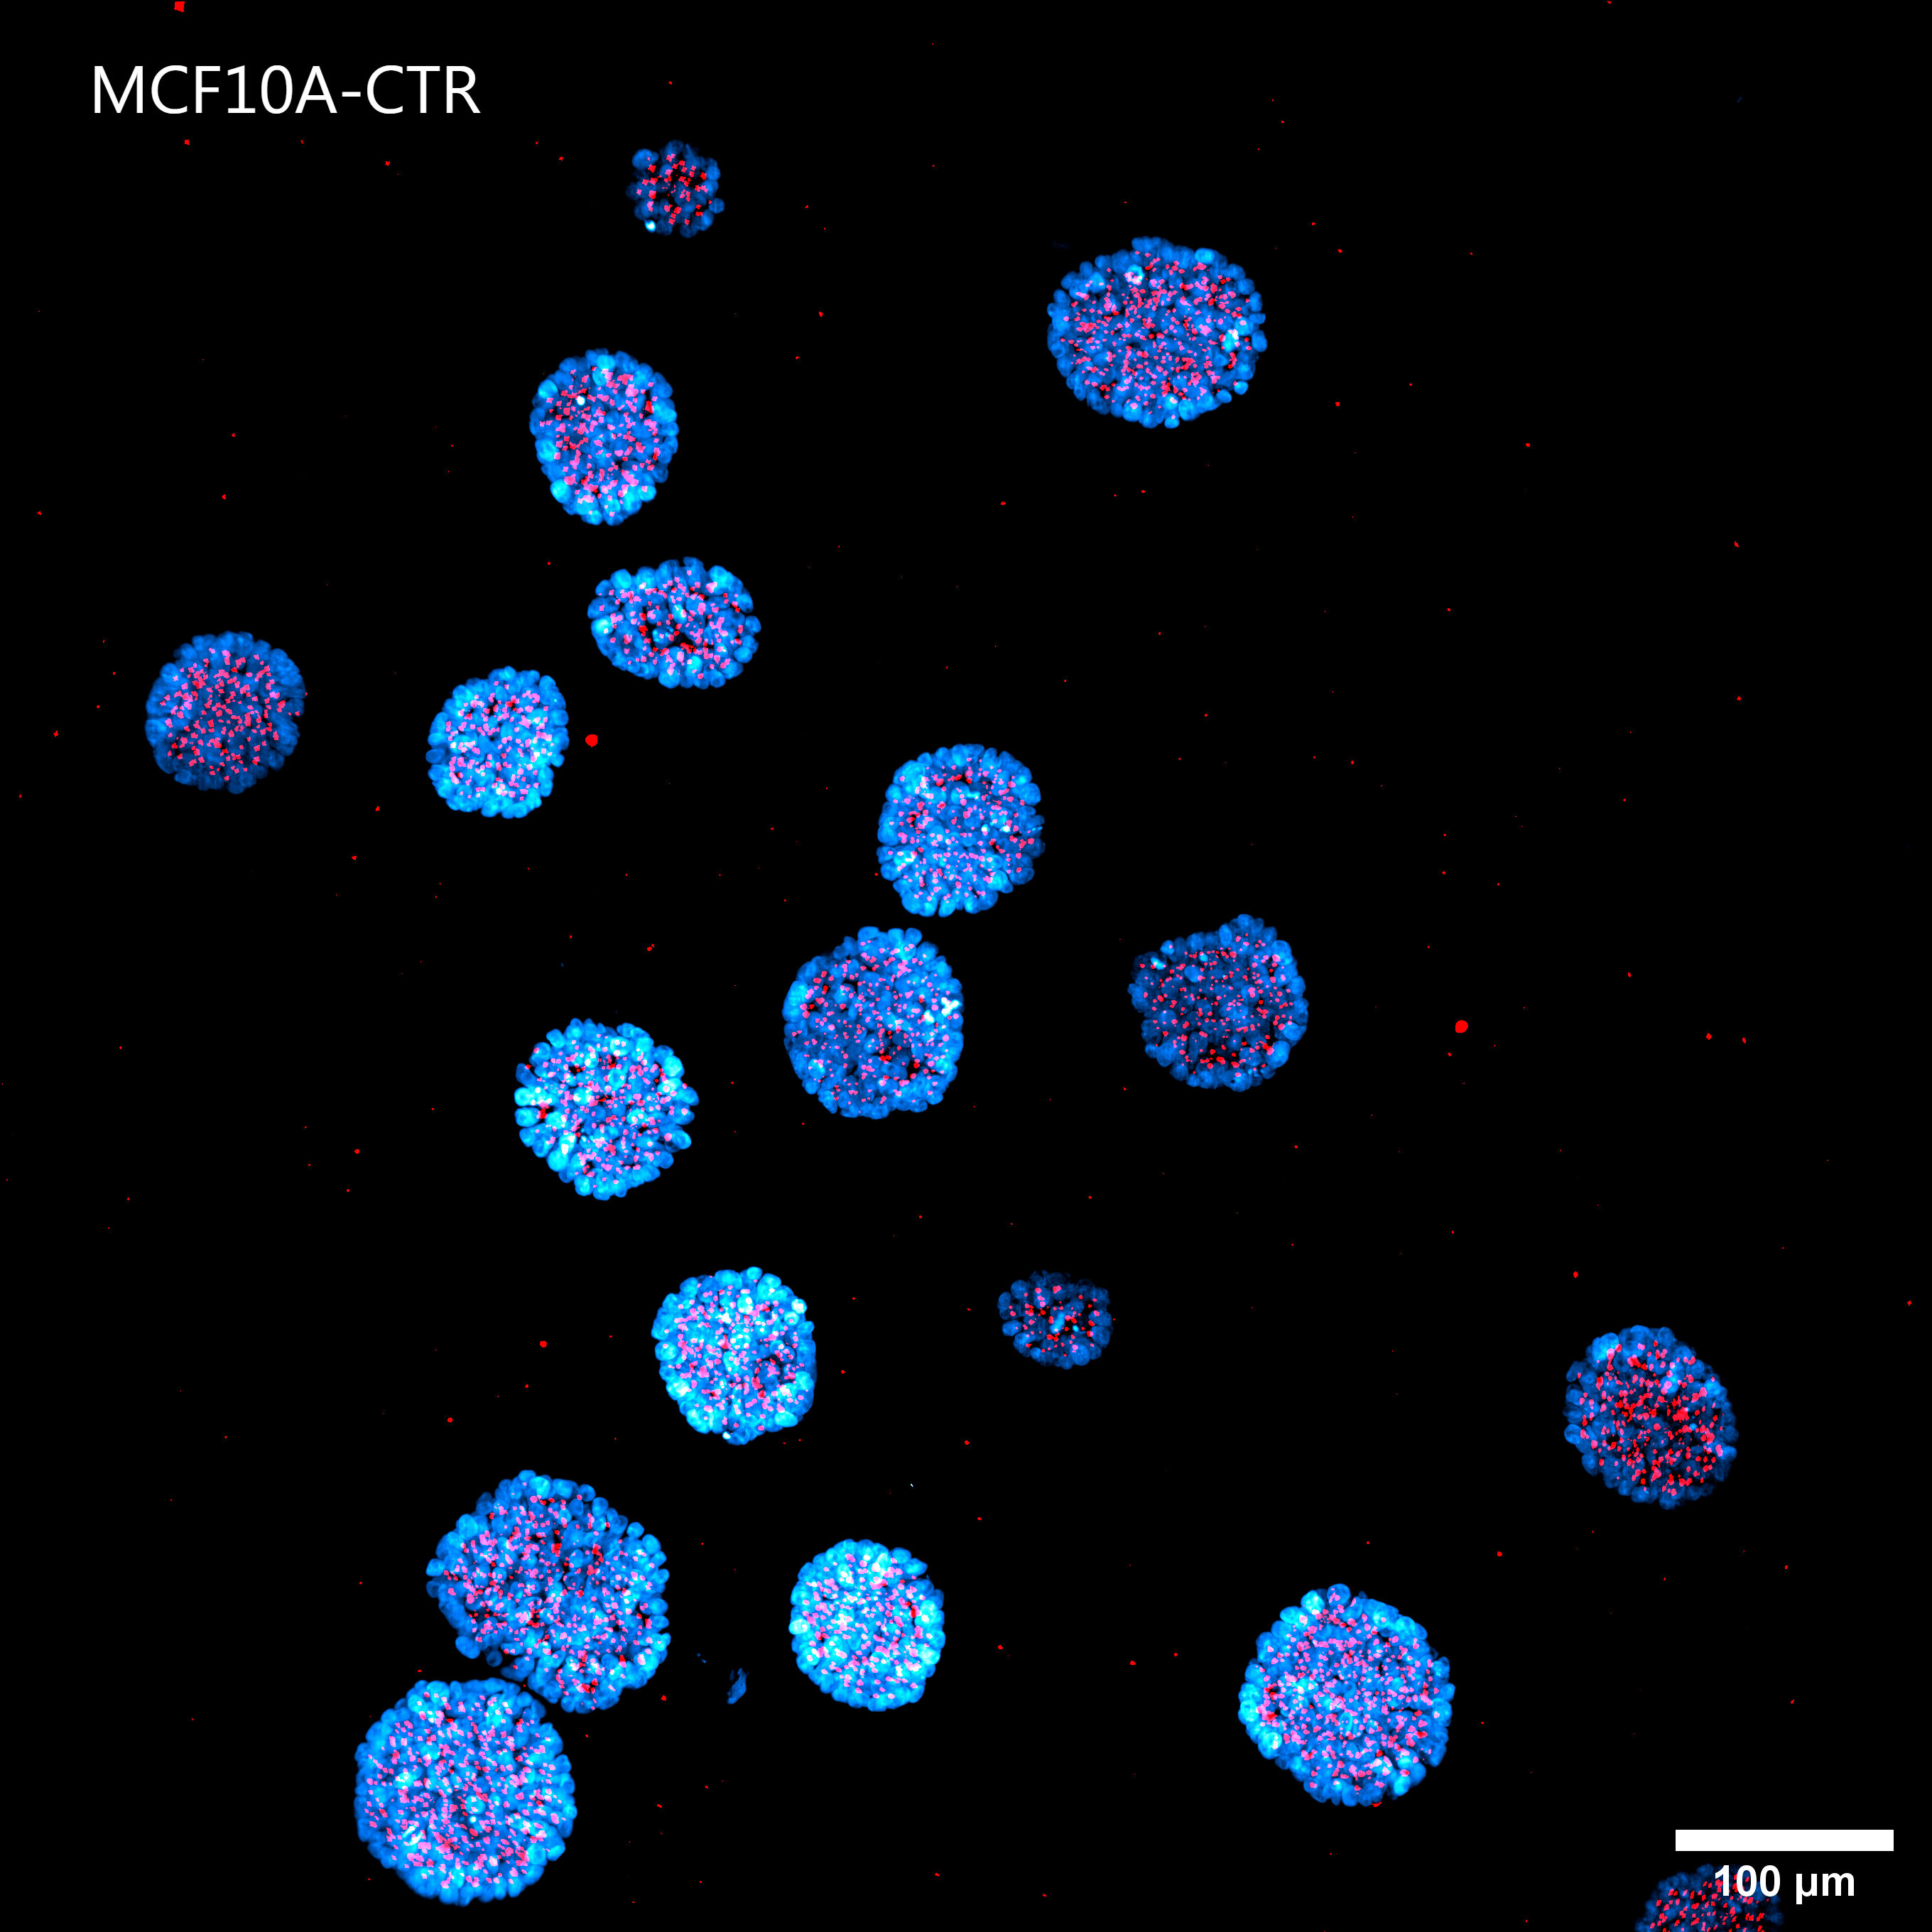

Figure 4 shows a maximum intensity projection (MIP) of 60 um Z-stack of non-malignant (A) and tumorigenic (B) acini. By providing homogeneous illumination over the entire 25 mm field of view (FOV), the X-Light V3 confocal spinning disk allowed us to analyze a large number of acini, reducing the number of images required to obtain robust data and, therefore, minimizing acquisition time.

A

Figure 4: MIP from 60 um Z-stack of non-malignant (A) and tumorigenic acini (B). Cells were cultured in 3D Matrigel suspensions and stained with pericentrin (red) and DAPI (blue). These images were acquired with a CFI Plan Apochromat Lambda D 20x air objective (20x, Nikon, 0.8 NA and 0.8 mm WD).

Matrigel matrix is crucial to support the growth of acini and for the proper formation of their 3D architecture; however, the embedding of the sample in such a dense and opaque matrix can make imaging more complicated. It is also possible for Matrigel preparations to have a high degree of autofluorescence, which reduces the signal-to-noise ratio. Despite these challenges, as demonstrated by the orthogonal projections shown in Figure 5 and by the volume view in Figure 6, the X-Light V3 confocal spinning disk allowed for obtaining excellent sectioning and image quality.